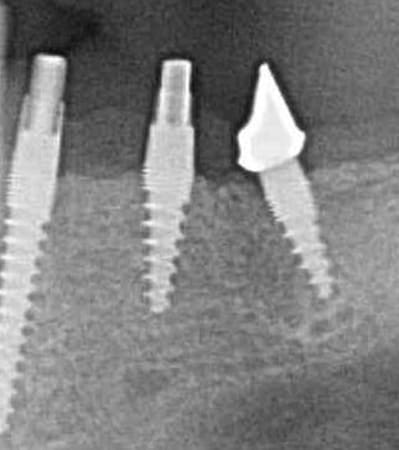

Oui,c´est un Prep cap zircone , que je cémente juste après l´implantation immédiate pour mieux former la gencive. Les implants monoblocs ont étés implantés entre 40 et 60 Ncm . Les photos 6 et 8 on voit les prep cap juste après l´implantation immédiate ce sont des sortes de "couronnes" pré fabriquées.

L'axe de la 45 me semble pas très conventionnel...

Oui , tu as raison pour la 45, en fait quand j´ai enlevé la 45 j´ai choisi l´axe comme ca ( dans l´os dur et en bon santé) parce que c´etait ici que je pouvais avoir la stabilité ( pour cet implant à 50 Ncm.

Voilà une patiente que je revois à deux ans apres la pose d'un monobloc Classic line 3,5/12mm et prep cap zircone 12 degres 2/2 en 24.

Radios 1,2,3 photo 1= jour de la pose de l'implant.

radio 4 photo 2 et 3= 8 semaines post pose de l'implant, ceramiques scéllées.